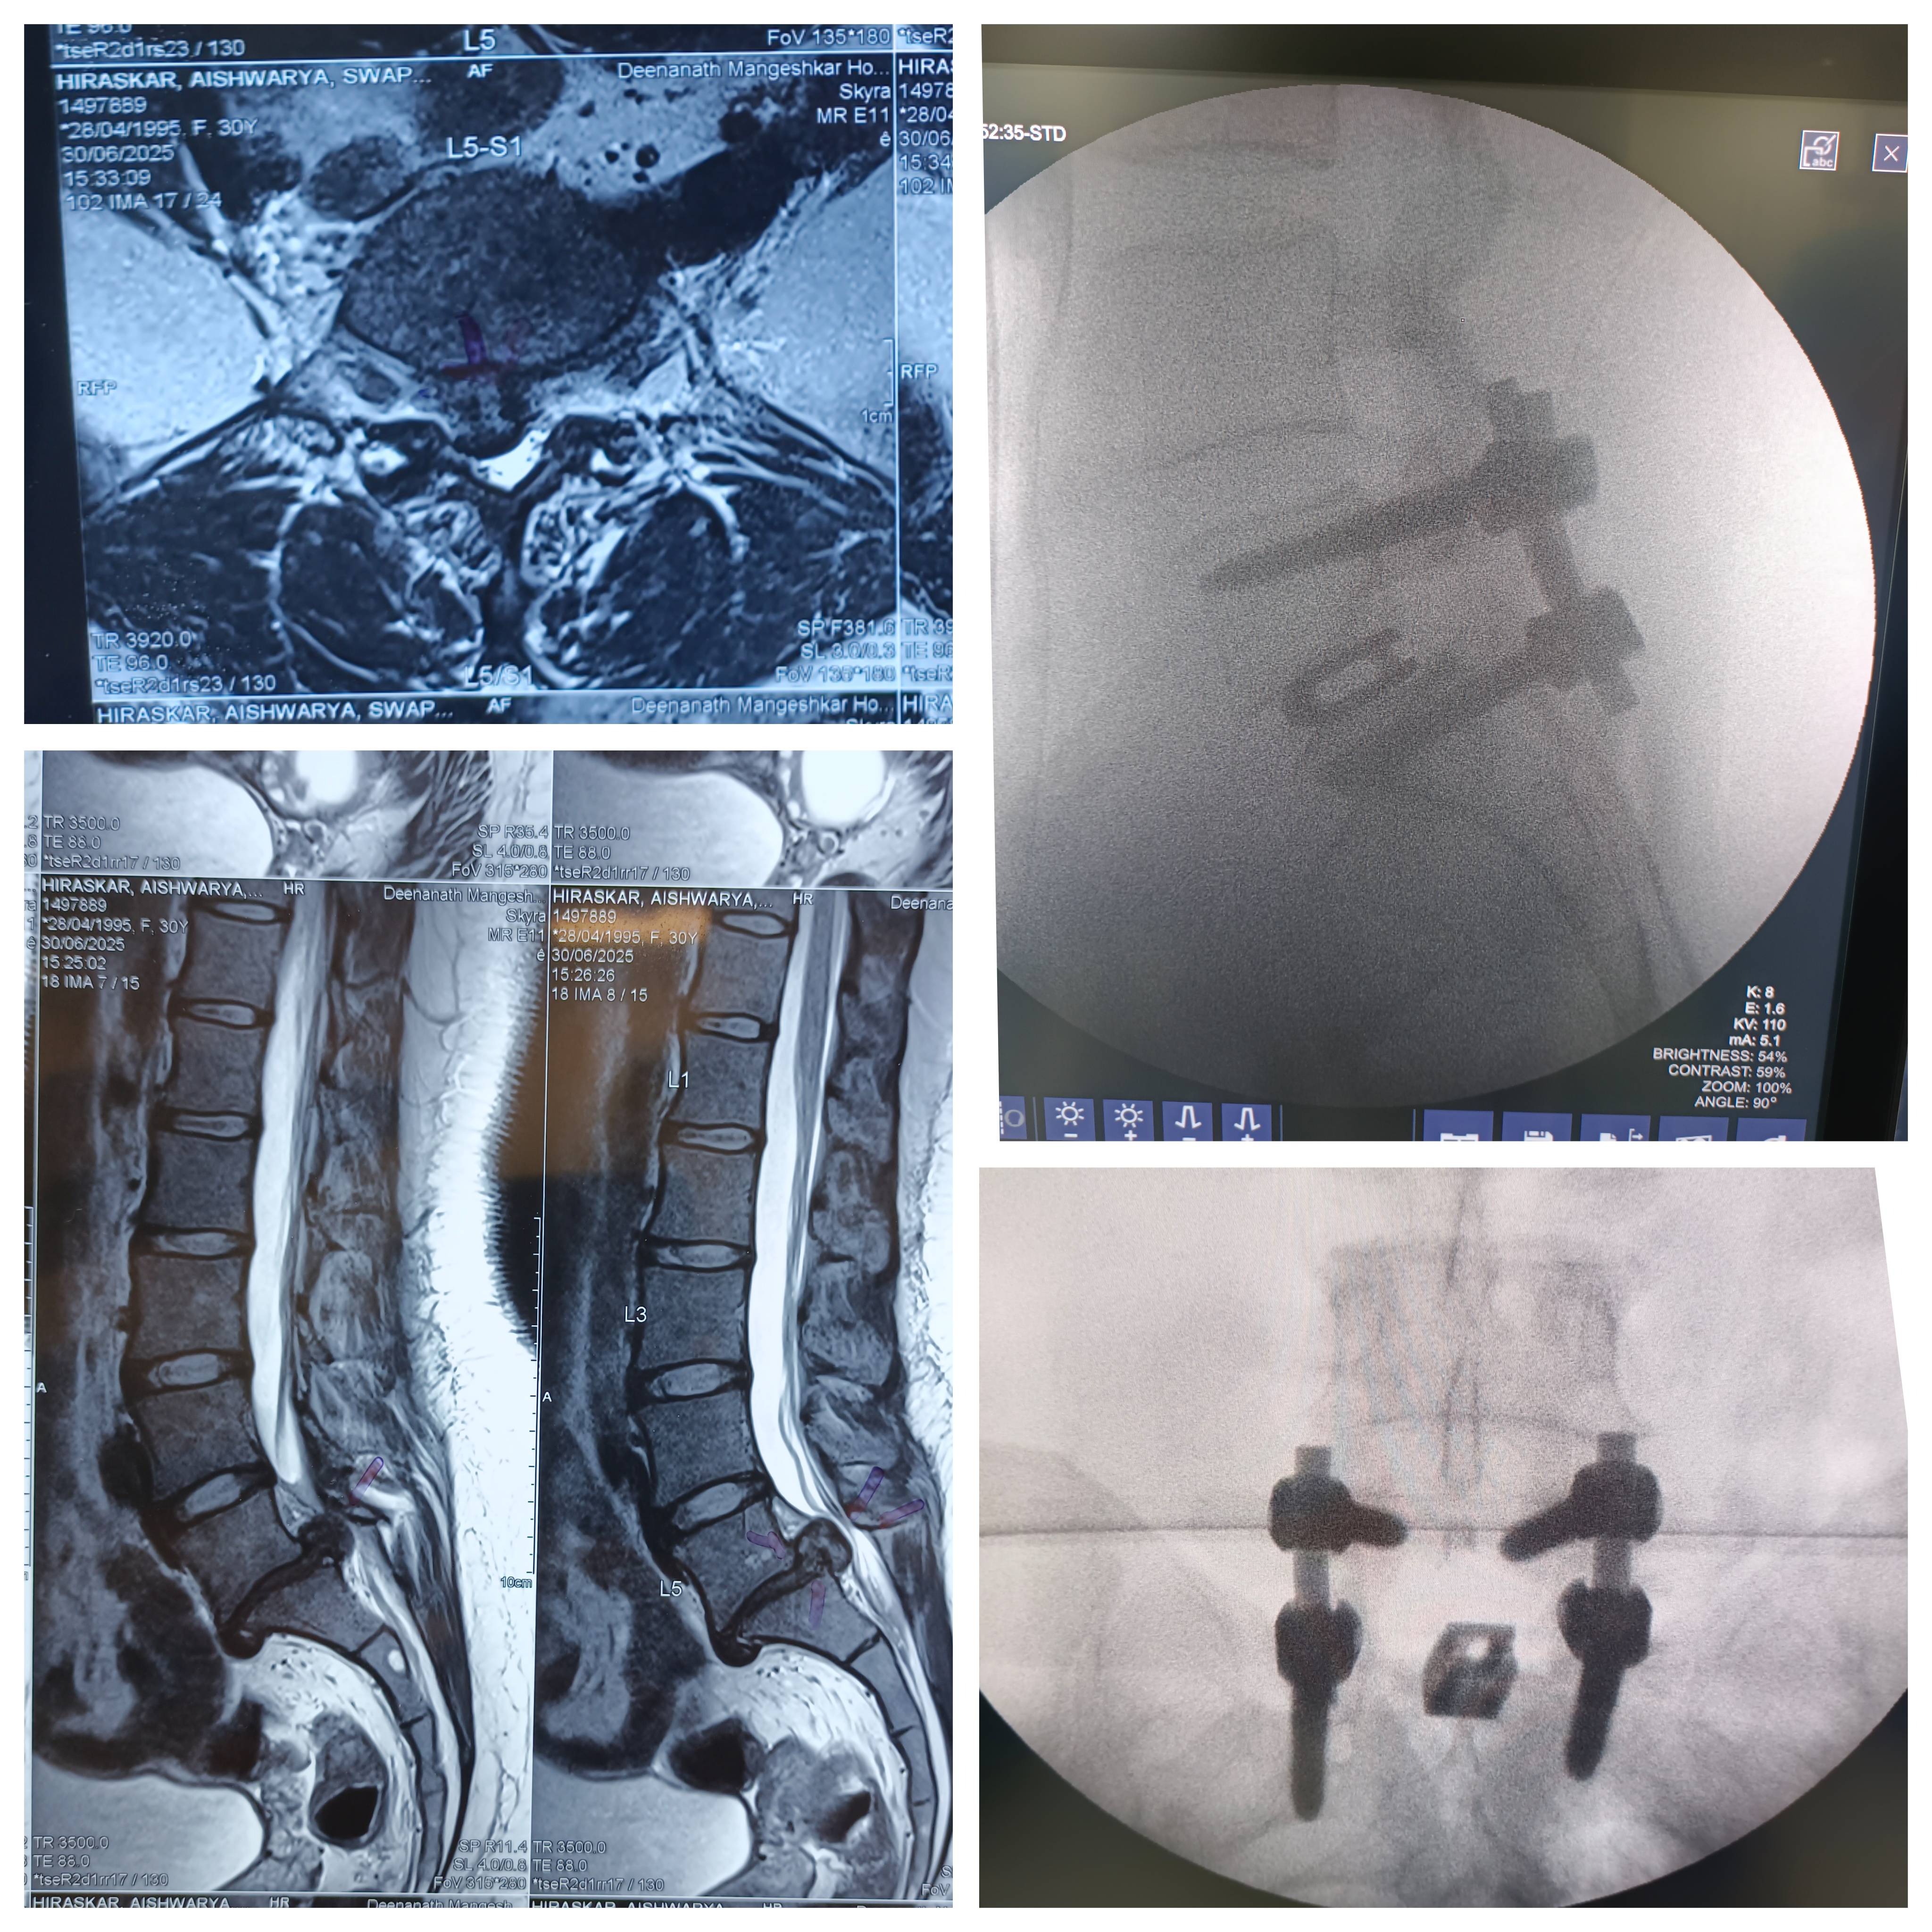

30-YEAR-OLD PATIENT WITH SEVERE LOW BACK PAIN, UNABLE TO WALK. MRI SHOWED L5 PARS INTER-ARTICULARIS DEFECT (PARS LYSIS) WITH L5-S1 DISC PROLAPSE WITH SEVERE SPINAL CANAL STENOSIS AND NERVE ROOT COMPRESSION. PATIENT UNDERWENT L5-S1 DISCECTOMY, LAMINECTOMY, DECOMPRESSION AND POSTERIOR SPINAL FIXATION/FUSION USING TITANIUM SCREWS, RODS, AND INTERBODY TITANIUM CAGE (MICROSCOPIC SPINE SURGERY). NERVE ROOTS FULLY DECOMPRESSED. COMPLETE DISC IS REMOVED AND INTERBODY TITANIUM CAGE / ARTIFICIAL DISC IS FIXED IN L5-S1 LEVEL. POST-OP RESULT: ✔ WALKING NEXT DAY WITH BELT ✔ NO LEG PAIN ✔ NO TINGLING/HEAVINESS ✔ COMFORTABLE SITTING ✔ DISCHARGED IN 2 DAYS ✔ CONTINUING EXERCISES #SUCCESSFULSPINESURGERY #LUMBARSPINESURGERY #LOWBACKSURGERY #LUMBARDISCPROLAPSE #LUMBARCANALSTENOSIS #LUMBARDISCHERNIATION #NERVEROOTCOMPRESSIONTREATMENT #SPINEFIXATION #SPINEFUSION #PARSLYSIS #L5S1SURGERY #MICROSCOPICSPINESURGERY #BEST SPINE SURGEON IN PUNE